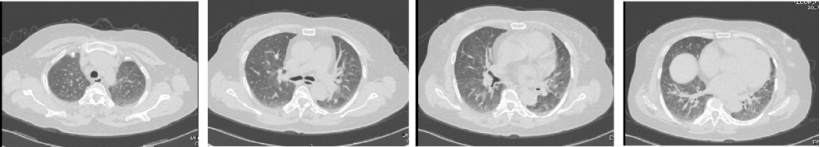

请风湿科会诊排除自身免疫病,予甲泼尼龙80 mg qd,气喘稍好转。行气管镜检查送检灌洗液G试验153.0 pg/ml,GM试验0.99。加用伏立康唑抗真菌治疗后当晚症状好转,1周后症状消失,复查胸部CT,病灶吸收(图4)。为何伏立康唑的“平喘”疗效会如此迅速?因为该患者的诊断是联合气道烟曲霉病——真菌敏感性重症哮喘+变应性真菌性鼻/鼻窦炎。

图4  病例2出院时胸部CT